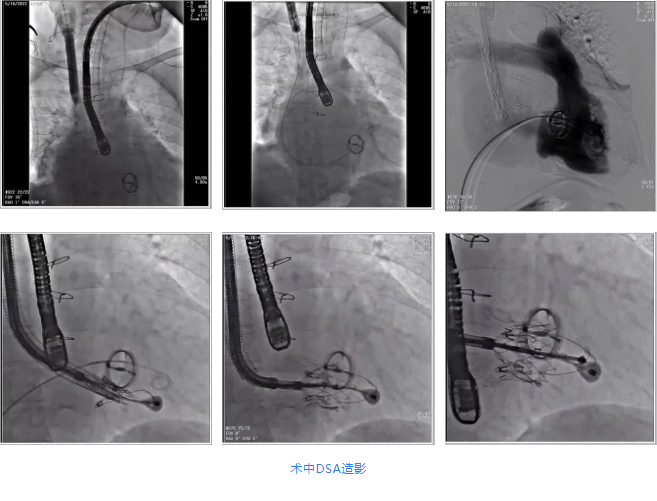

根據(jù)術(shù)前評估結(jié)果,郭應(yīng)強教授團(tuán)隊為患者量身定制了手術(shù)策略,決定使用LuX-Valve Plus經(jīng)血管三尖瓣置換系統(tǒng)開展手術(shù)治療。手術(shù)在全麻下進(jìn)行,采用經(jīng)右側(cè)頸靜脈入路,在經(jīng)食道超聲和DSA的指引下調(diào)整輸送器角度以達(dá)到正確位置,勾住前瓣后逐步釋放盤片,盤片打開后順利扎針,最終完成瓣膜植入,輸送器撤出。術(shù)后超聲提示人工三尖瓣同軸性良好,瓣架固定牢靠,無反流和瓣周漏,術(shù)后三尖瓣平均跨瓣壓差為1 mmHg。